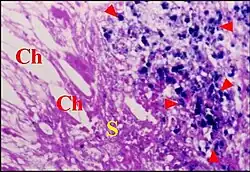

Otite moyenne

Lésion prédominante, elle est caractérisée au début par un simple œdème du stroma et une vaso-dilatation de ses capillaires. Un infiltrat inflammatoire non spécifique apparait ensuite dans le même stroma. Cet infiltrat se compose de polynucléaires neutrophiles, lymphocytes B, plasmocytes, mastocytes et histiocytes. Il peut former un ou plusieurs foyers granulomateux avec des capillaires néoformés, des fibroblastes et des hémorragies localisées.Des polynucléaires et cellules de Langherans en émigrent vers l’épithélium malpighien sus-jacent où leurs vimentine et proteine S100 permettent de bien les mettre en évidence. L’afflux de ces cellules inflammatoires peut entrainer des ruptures épithéliales spontanées (ulcérations) et confirme leur agressivité envers le revêtement malpighien[8].

Le stroma granulomateux ainsi mis à nu peut s’épaissir en un ou plusieurs bourgeons charnus dont la protrusion forme un « polype otique » ou « aural ». Localisée ou diffuse, modérée ou sévère, l’inflammation ne se limite pas aux zones évolutives du cholestéatome[8]). De plus, elle peut affecter la chaine ossiculaire sous-jacente et, dans certains cas, les prothèses qui y ont été insérées.